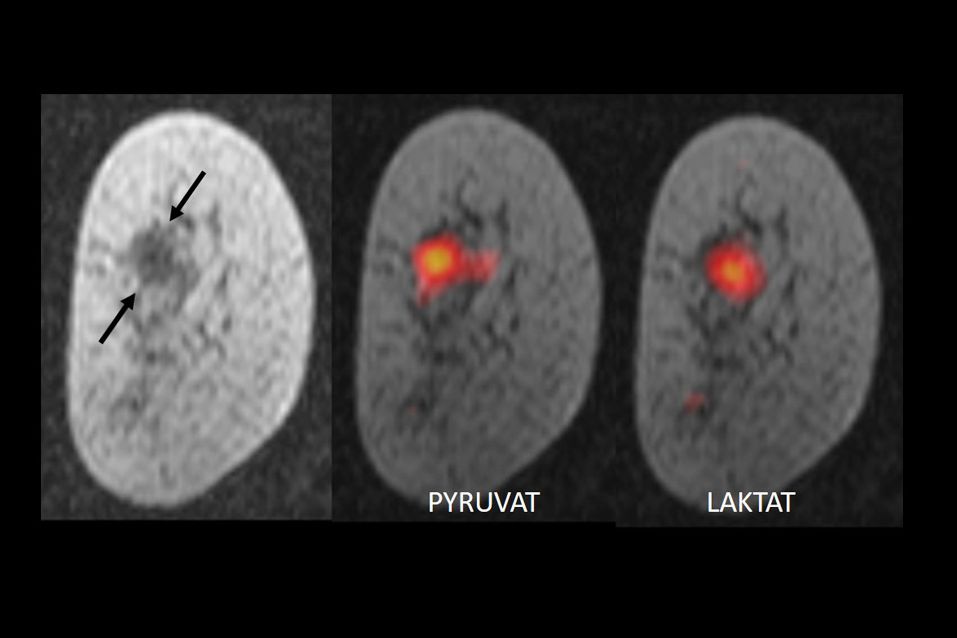

Die Gruppe an der Universität Cambridge hat die im Körper vorkommende Substanz Pyruvat mit dem nicht radioaktiven Kohlenstoffisotop C-13 markiert und diese magnetisiert. Dazu wird das markierte Pyruvat auf minus 272 Grad Celsius abgekühlt und einem sehr starken Magnetfeld und Mikrowellenstrahlung ausgesetzt – dieser Prozess wird auch "Hyperpolarisierung" genannt. Nachdem die Substanz wieder aufgetaut ist, wird sie Patientinnen injiziert. Durch die Magnetisierung erhöht sich die Signalstärke des C-13-Pyruvat im MRT um das 10.000-Fache, sodass innerhalb von Sekunden MRT Bilder des Tumorstoffwechsels angefertigt werden können. Üblicherweise wandeln Körperzellen Pyruvat in Laktat um. Da Tumorzellen einen veränderten Stoffwechsel aufweisen, erfolgt dort die Umwandlung von Pyruvat zu Laktat viel schneller – wobei die Geschwindigkeit des Prozesses zwischen verschiedenen Tumoren und auch innerhalb des Tumors variiert. Mit dem MRT lässt sich nicht nur die Menge des speziell behandelten Pyruvat in verschiedenen Geweben, sondern auch der Umwandlungsprozess in Echtzeit verfolgen. Die ForscherInnen zeigten, dass sich dadurch auf die Art des Tumors und dessen Aggressivität rückschließen lässt.

"Das ist eines der detailliertesten Bilder des Stoffwechsels von Brustkrebs, die wir je hatten. Es ist als ob wir den Tumor atmen sehen können", erklärt Kevin Brindle vom Cancer Research UK Cambridge Institute, einer der Begründer der Methode, in einer Aussendung.